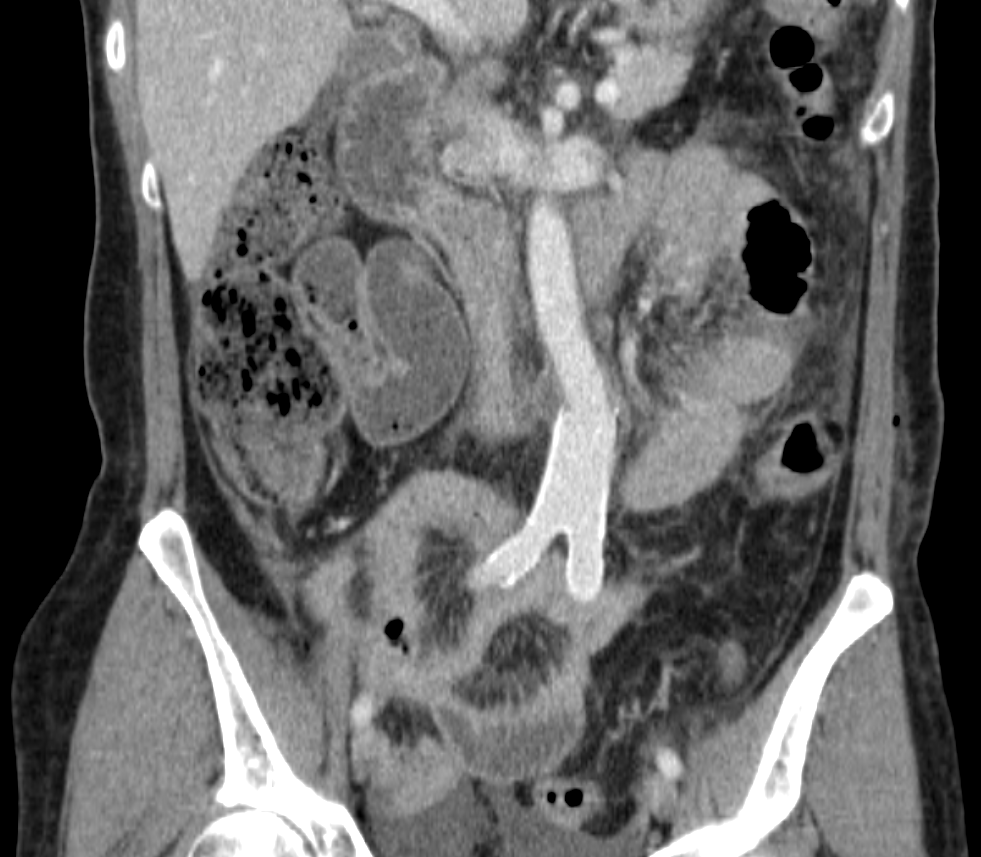

6. Рис. 6. КТ-ангиография органов брюшной полости после операции, артериальная фаза, фронтальная проекция. Примечание: рисунок выполнен авторами | |